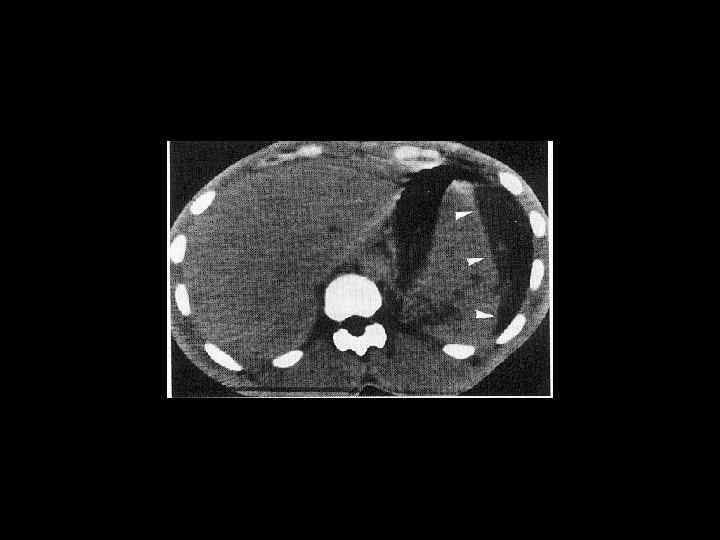

АКТУАЛЬНЫЕ ВОПРОСЫ РЕНТГЕНОЛОГИИ ЛУЧЕВАЯ ДИАГНОСТИКА ЗАБОЛЕВАНИЙ СЕЛЕЗЕНКИ Травма и инфаркт селезенки